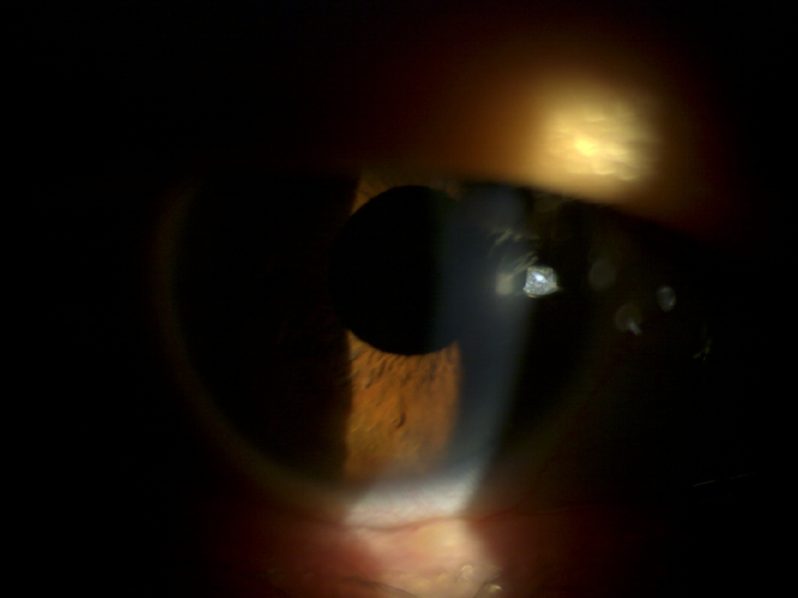

인공수정체 탈구 : 칸나브라바 공막고정수술

54세 남성 환자 사례

수술 8개월 후 나안시력 0.9

수술 전

수술 후

※ 해당 이미지는 본원에서 직접 촬영한 사진입니다.